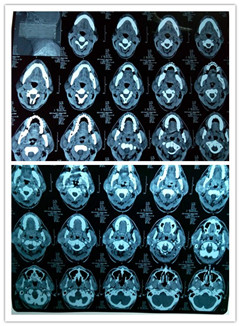

患者XXX,男性,38岁,发现右侧耳垂下两个渐增大肿物1年余,就诊我院耳鼻咽喉头颈外科。患者右侧耳垂下腮腺区可见局限性隆起,触及两个硬性结节,大小分别约2.0x1.5cm, 1.0x1.5cm,表面皮肤无红肿,无触及波动感及触压痛,活动度可,无破溃、流脓、出血。 入院后积极完善术前检查:彩超提示:右侧腮腺低回声结节,腮腺CT提示:右侧腮腺多发性结节灶,富血供病灶,余检查未见无异常.